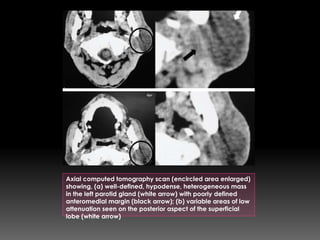

Axial computed tomography scan (encircled area enlarged)

showing, (a) well-defined, hypodense, heterogeneous mass

in the left parotid gland (white arrow) with poorly defined

anteromedial margin (black arrow); (b) variable areas of low

attenuation seen on the posterior aspect of the superficial

lobe (white arrow)